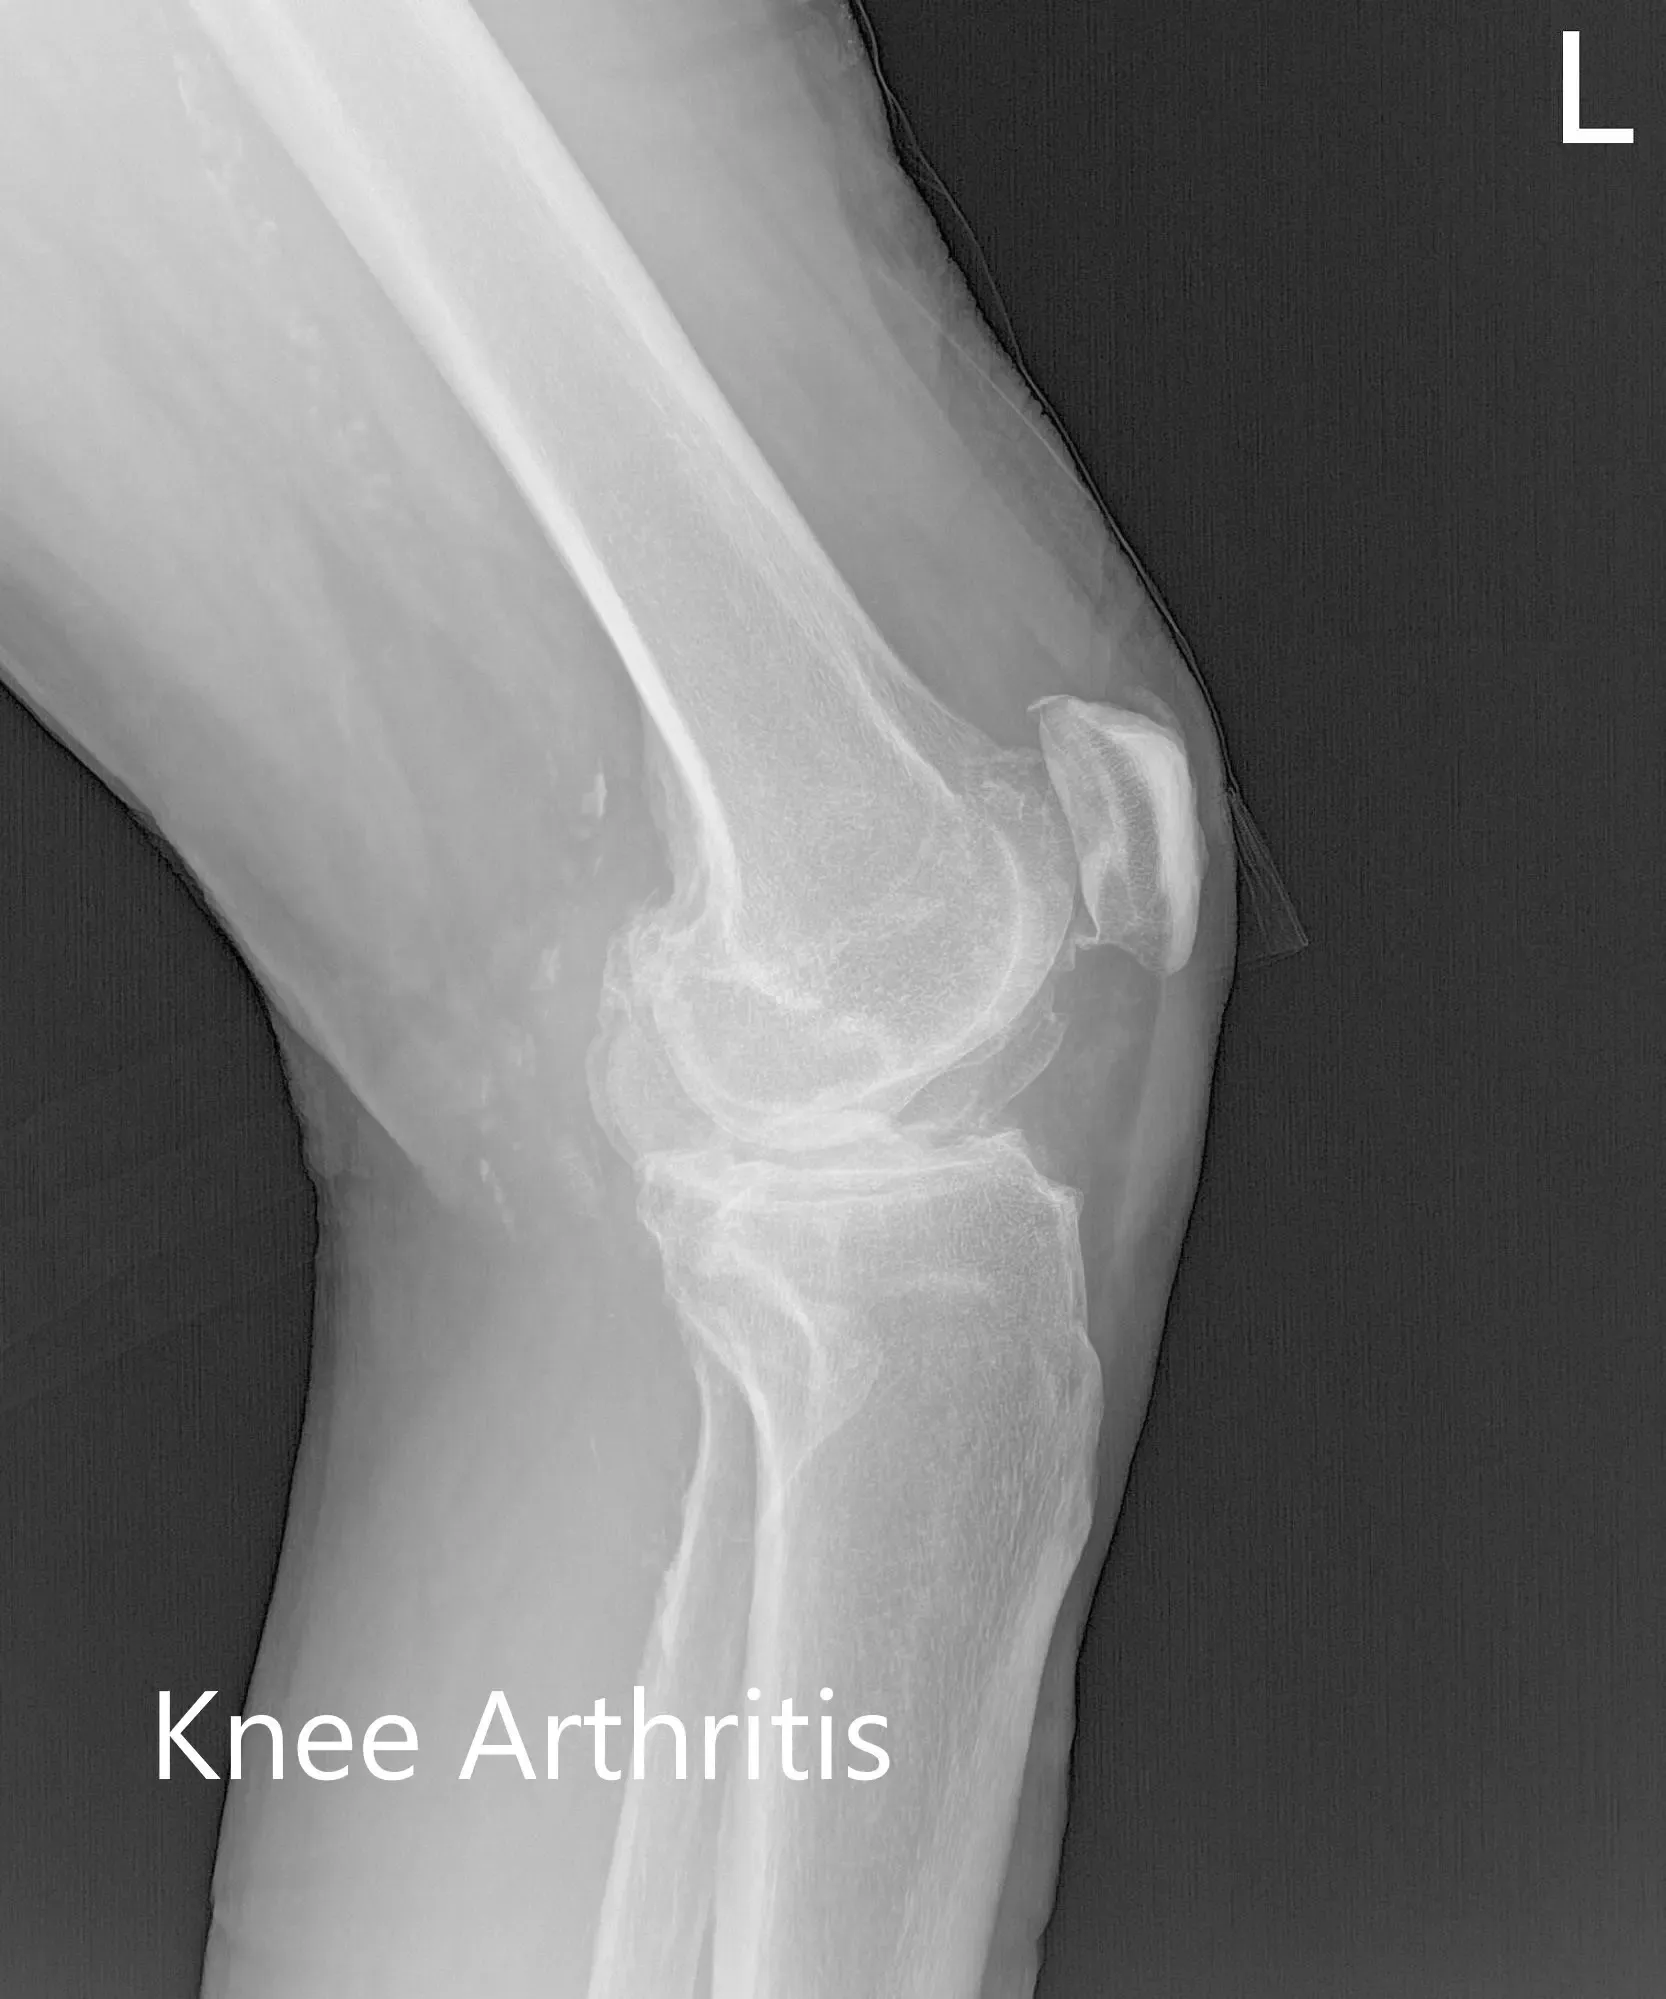

There was no distal neurological deficit and the bilateral pulses were good volume and comparable. Imaging studies revealed severe tricompartmental osteoarthritis of the left knee. Considering the patient’s lifestyle limiting knee pain, she was advised customized left knee total replacement. Risks, benefits, and alternatives were discussed with her at length. She agreed with the plan.

Preoperative X-ray of the left knee showing AP, lateral and merchant views